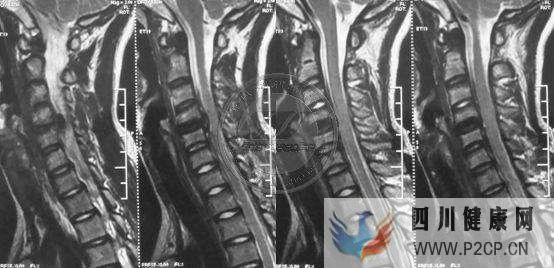

2、无弹性、限制性的硬脊膜压迫、Konno等认为平山病是异常的硬脊膜牵拉限制作用,不仅在直立位时影响,而且在屈颈时加重脊髓的损伤。颈脊膜的松解成形手术明显的近期和远期效果也证实了这一观点,可见这是平山病发病因素。